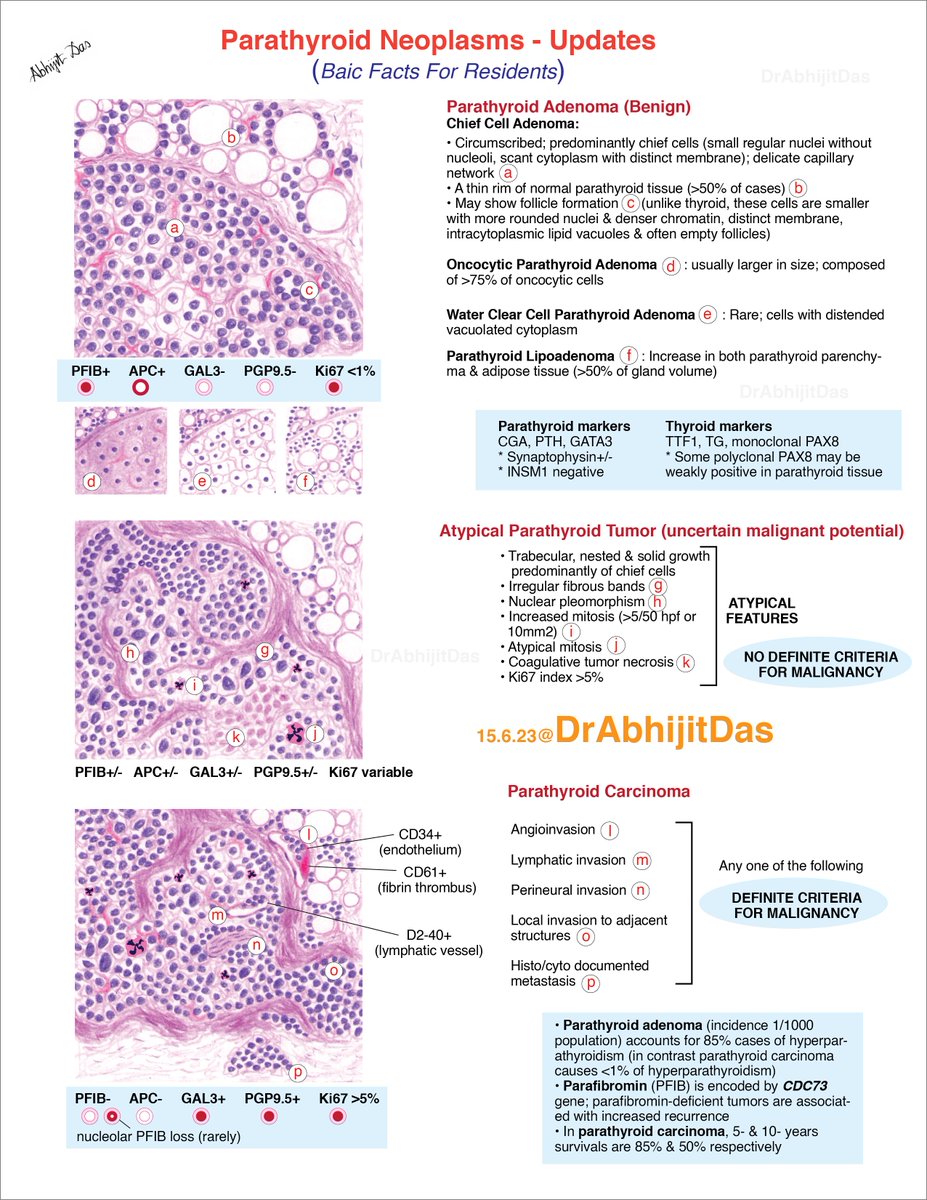

1 slide diagnosis #PathTwitter #pathboards Swathi Prabhu, MD Padma Priya J Carlos Miguel Ruiz Arunima Deb, MD